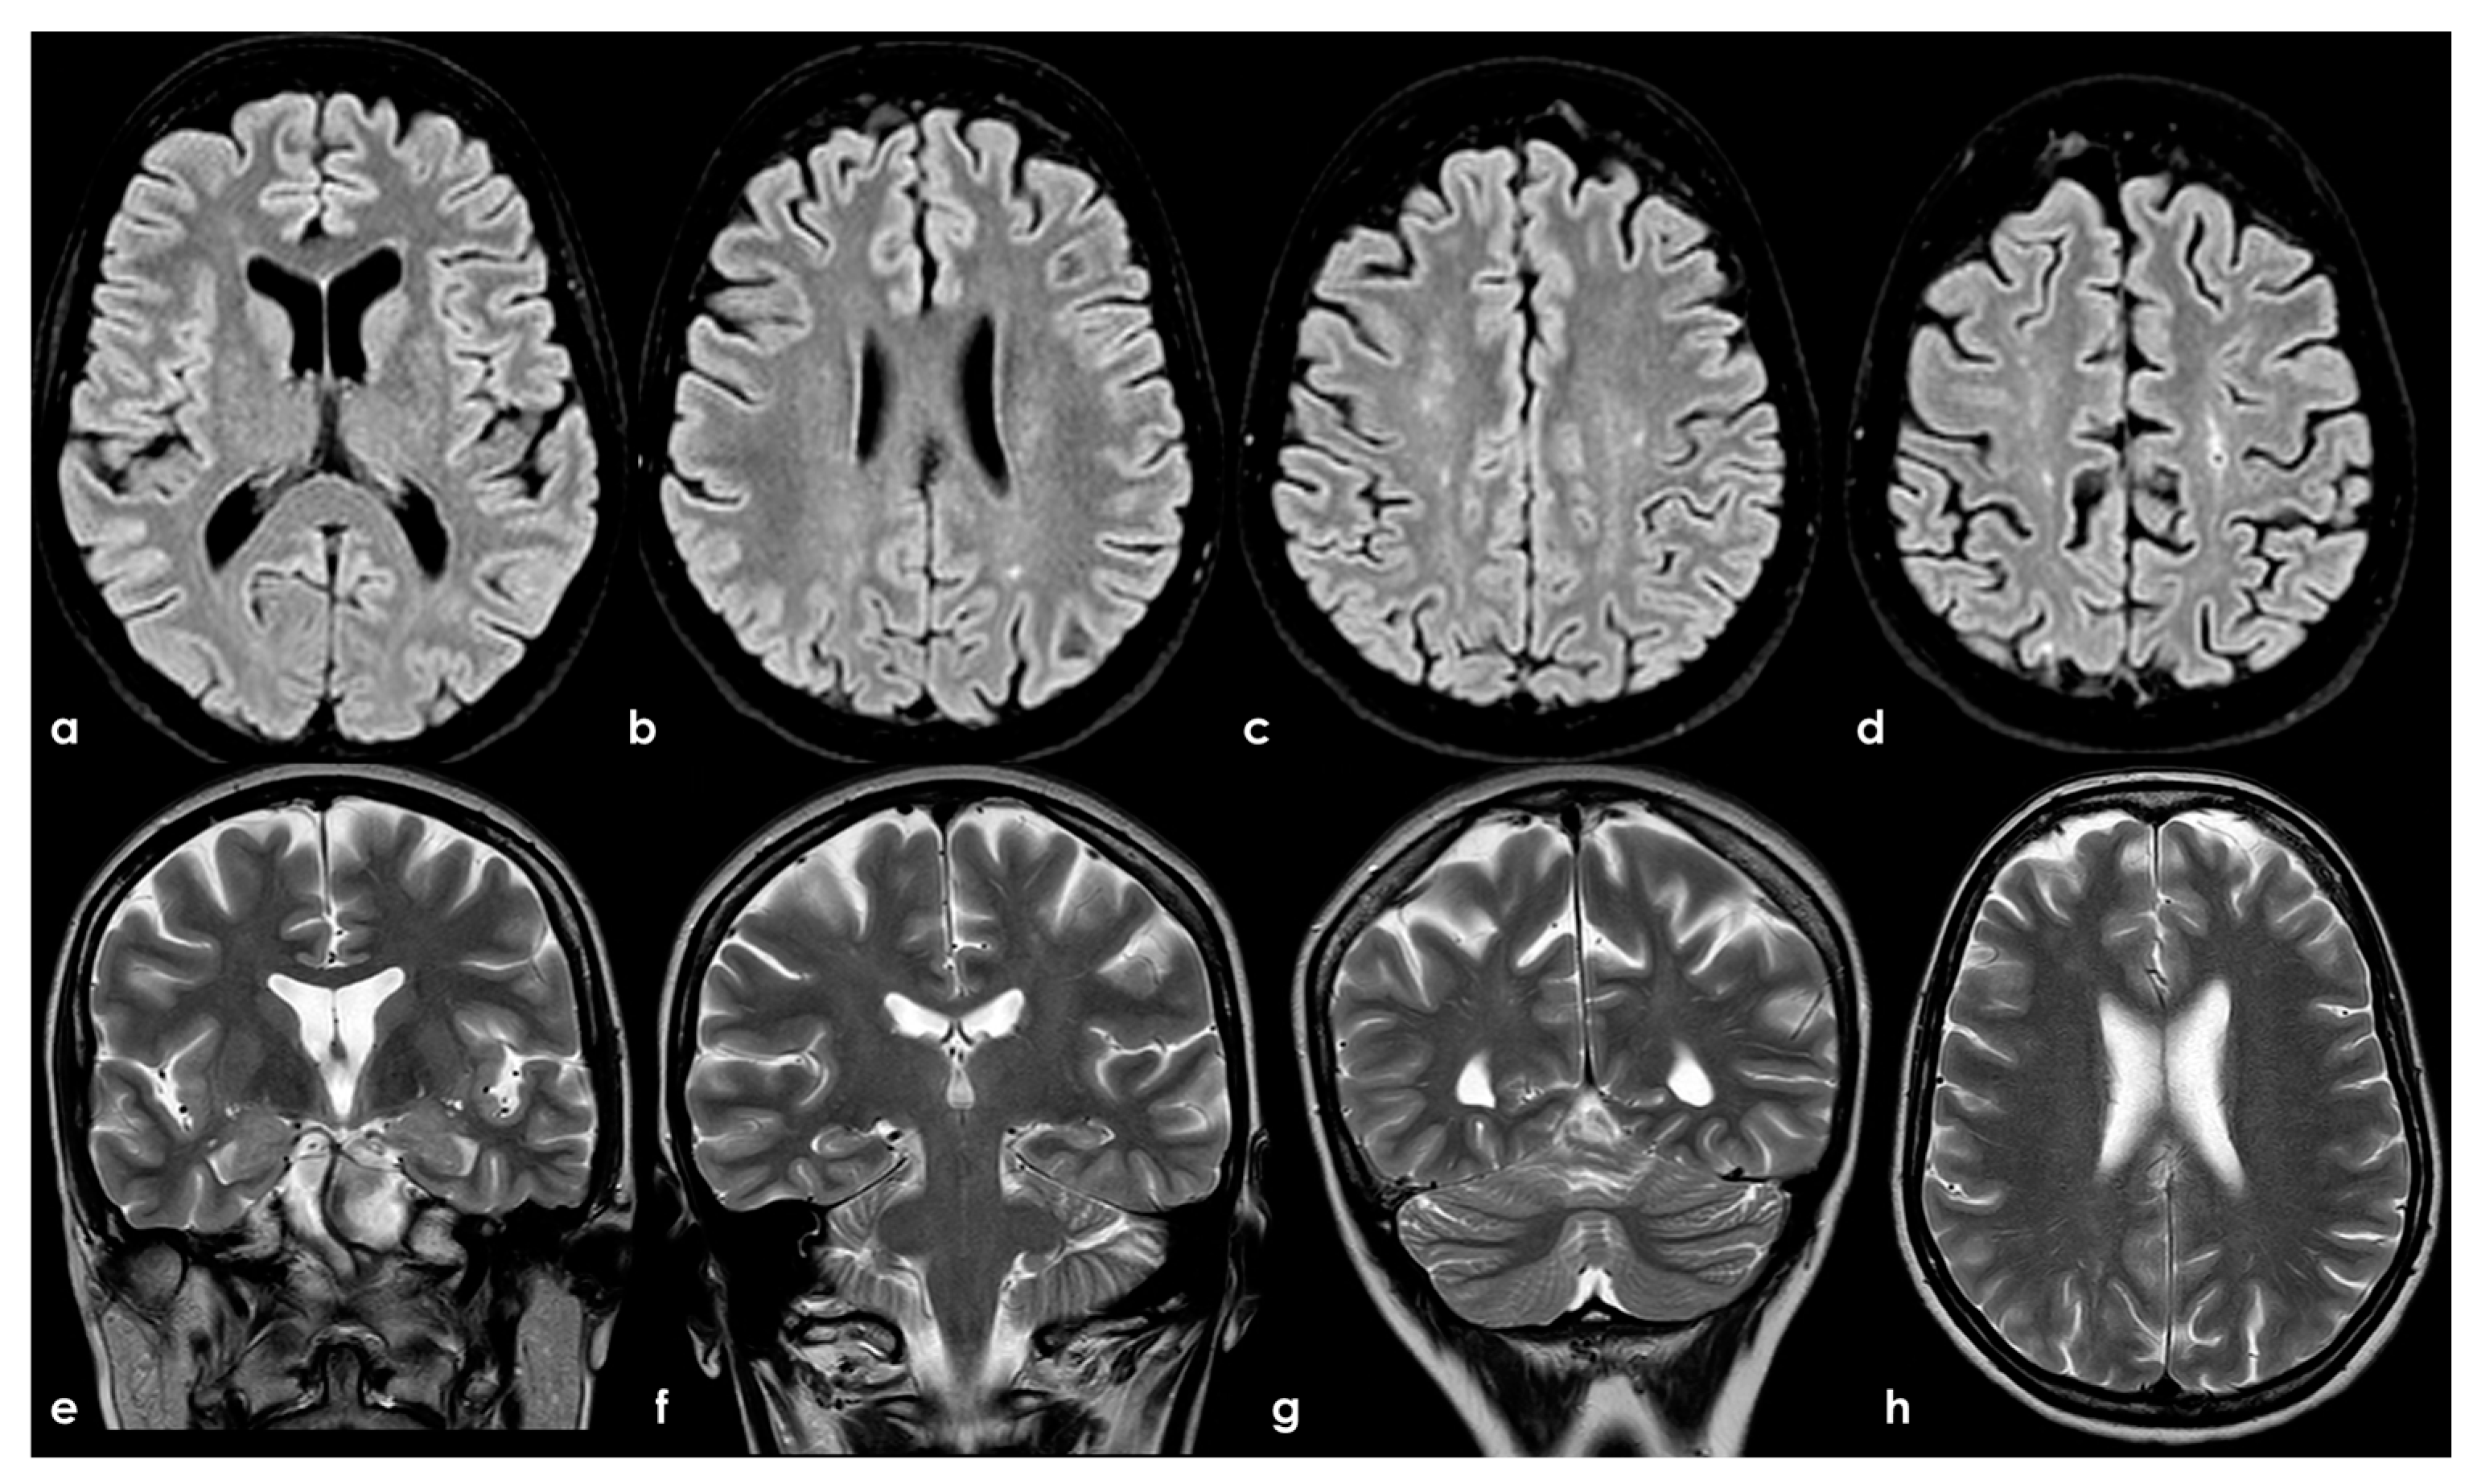

4.2.1. Small-Vessel Disease